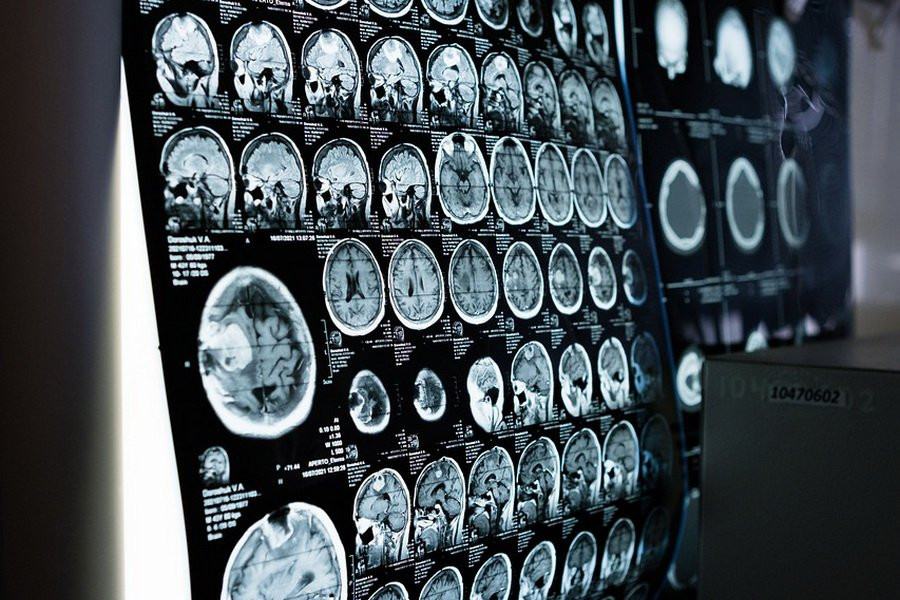

В статье, опубликованной в журнале HealthDay, раскрывается интересная взаимосвязь между уровнем сахара в крови и темпами старения мозга. Согласно проведенному анализу МРТ-снимков более 31 тысячи британцев в возрасте от 40 до 70 лет, была выявлена четкая закономерность: у людей с диабетом 2-го типа мозг в среднем был на 4 года старше, чем у их здоровых сверстников.